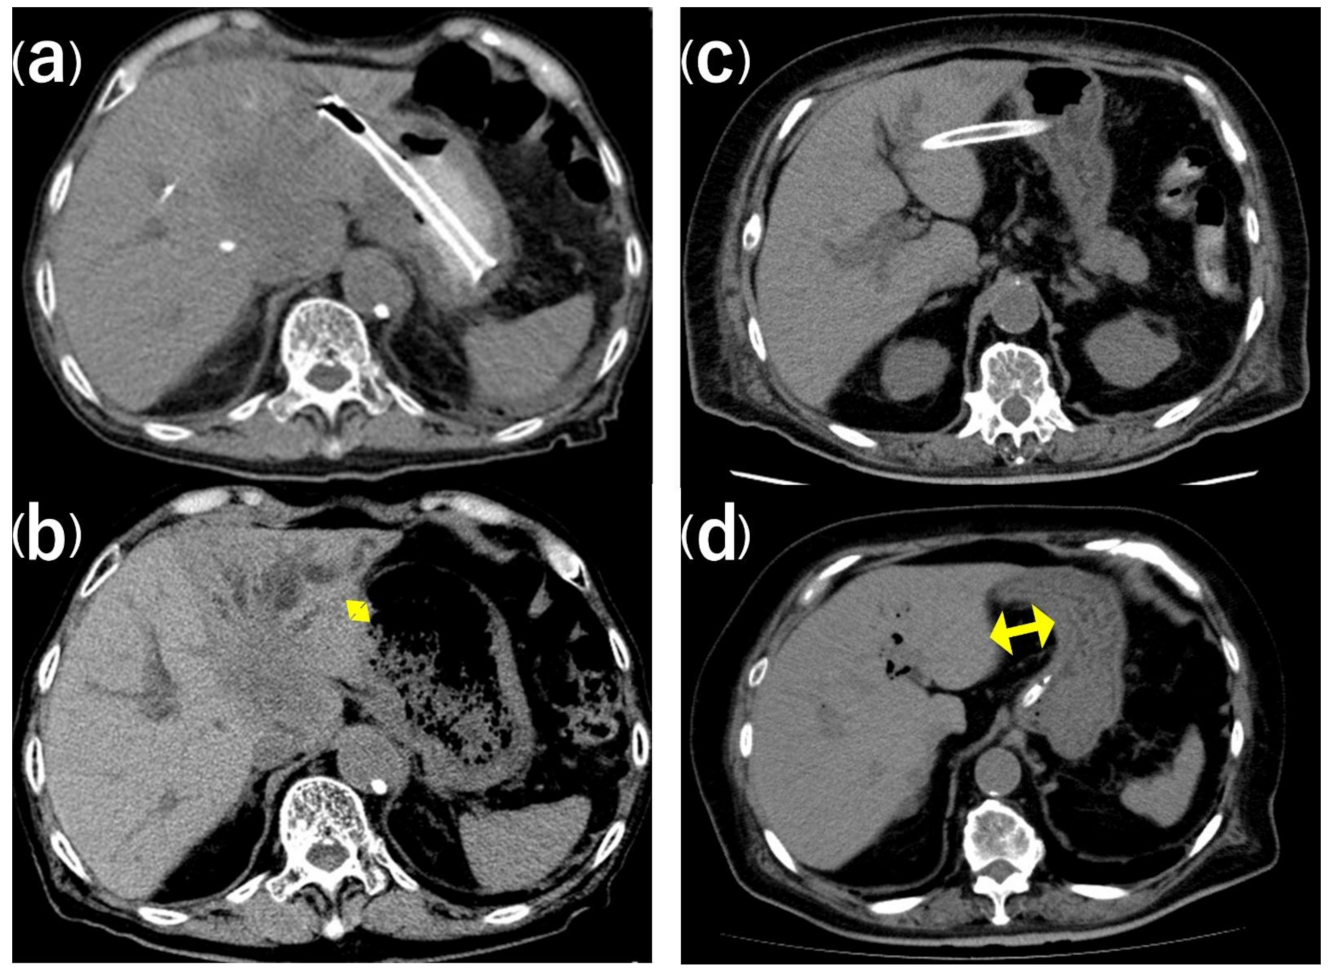

4. Discussion